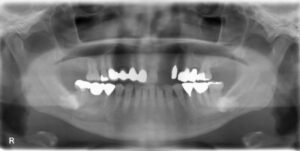

上顎前歯2本欠損症例

BEFORE AFTER 52歳女性/上2本欠損/インプラント埋込手術 【治療内容】 上顎前歯のグラつきが主訴でご来院の…